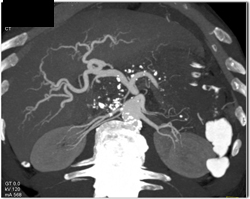

1 Cm Pancreatic Cancer With Dilated Pancreatic Duct